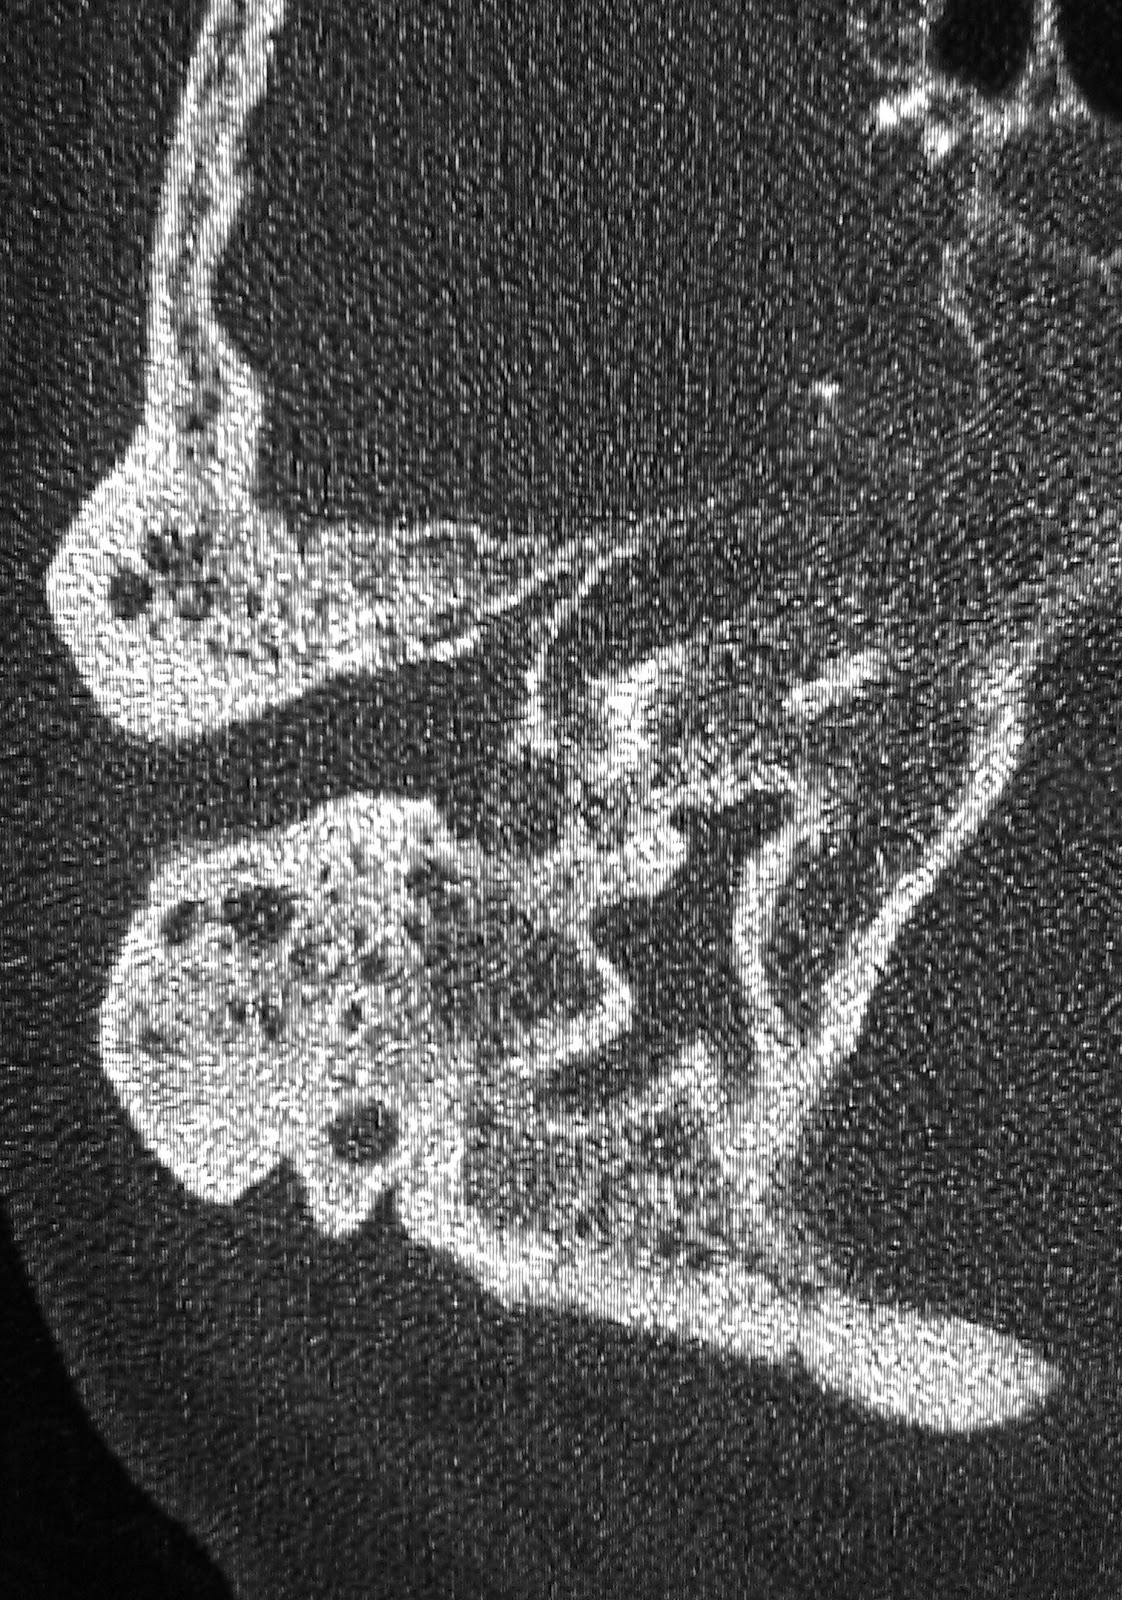

Malignant External Otitis Ct Evaluation